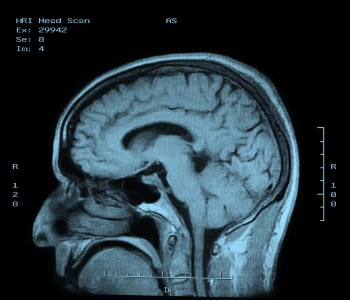

Magnetic Resonance Imaging

Magnetic resonance imaging (MRI) is a completely different way of viewing inside parts of the body. It relies on the way hydrogen nuclei respond to magnetic fields. Functional MRI (fMRI) is a specialized version used in the brain, tracking oxygen instead to image blood flow based on oxygenation levels.

This process works by placing the body in a strong static magnetic field so that all the nuclei are oriented in the same direction. A varying field is then created to perturb the atoms locally; this re-orients them from their starting position. When that varying field is removed, the cell processes back to the static position. Different cells relax at different rates, ranging from tens of milliseconds to over one second, and the decay signals given off as the cells move back – in the 1 to 300 MHz range – create the image (see Figure 5). It is these differences in the relaxation timing that allow the system to discriminate different kinds of tissues.

Figure 5: MRI image of the brain.